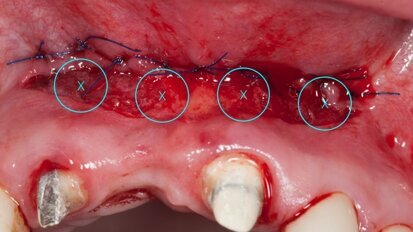

Autotransplantacja jako metoda autogennej rekonstrukcji ubytków wyrostka zębodołowego

Jedną z metod leczenia braków w uzębieniu stałym jest autotransplantacja. Przeszczepienie zawiązka zęba zapewnia jego wyrzynanie i utrzymanie ...

zapisz